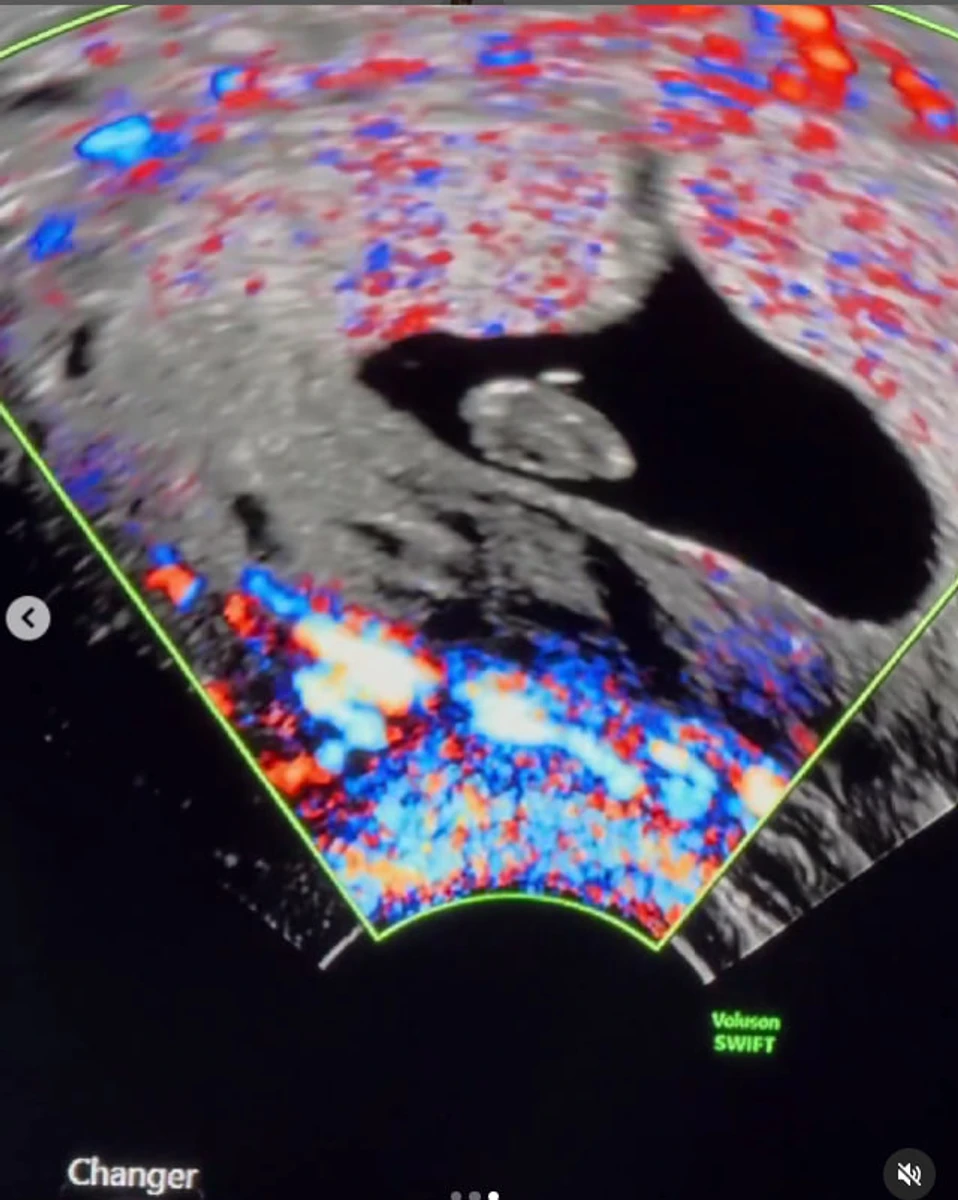

Вже 4 жовтня Юлії та Павлу повідомили, що серце їхньої майбутньої дитини перестало битися.

"Важко описати біль. Ми вже так звикли до цієї ідеї. Йшов 10-й тиждень. 05.10.24. День операції. Це було швидко, майже без фізичного болю. Тепер настав час одужати. Ми встигли впоратися з багатьма викликами одразу. Але для малюка це було забагато", - підсумувала дівчина.

У лікарні дівчині зробили УЗД та повідомили про завмерлу вагітність